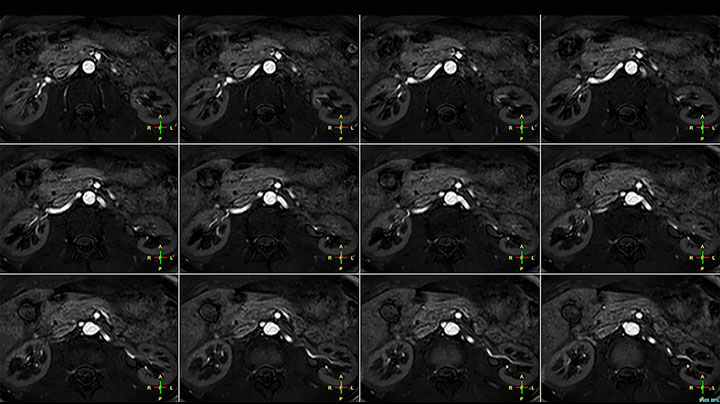

Non-contrast MRA of renal arteries

Imaging the renal arteries without contrast agent on Prodiva 1.5T.